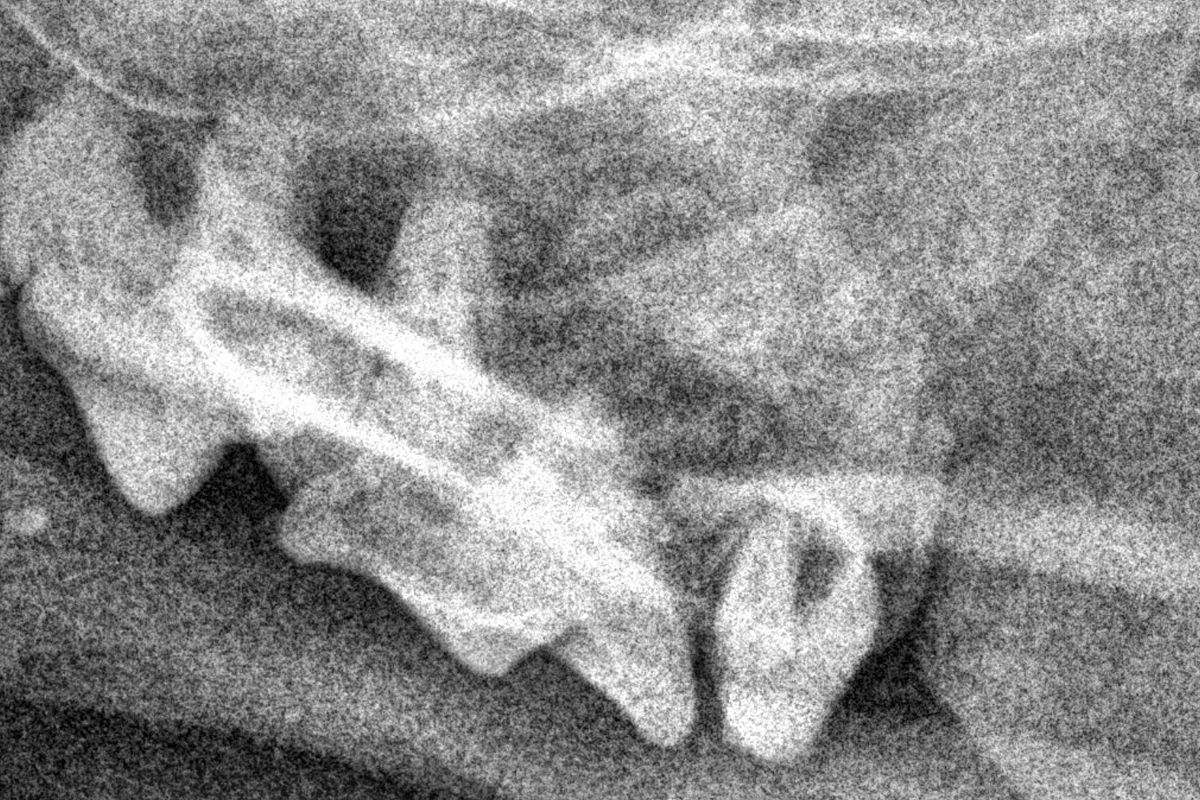

Кошка британская, рентген

Тем не менее, на стадии разрушения коронки зуба и ее эмали, а так же разрушение цемента корня зуба, реальной помощью пациенту будет удаление этих зубов, это является сложной процедурой и должна проводиться только опытными ветеринарными стоматологами с обязательной рентгенографической диагностикой во время проведения процедуры удаления зубов.